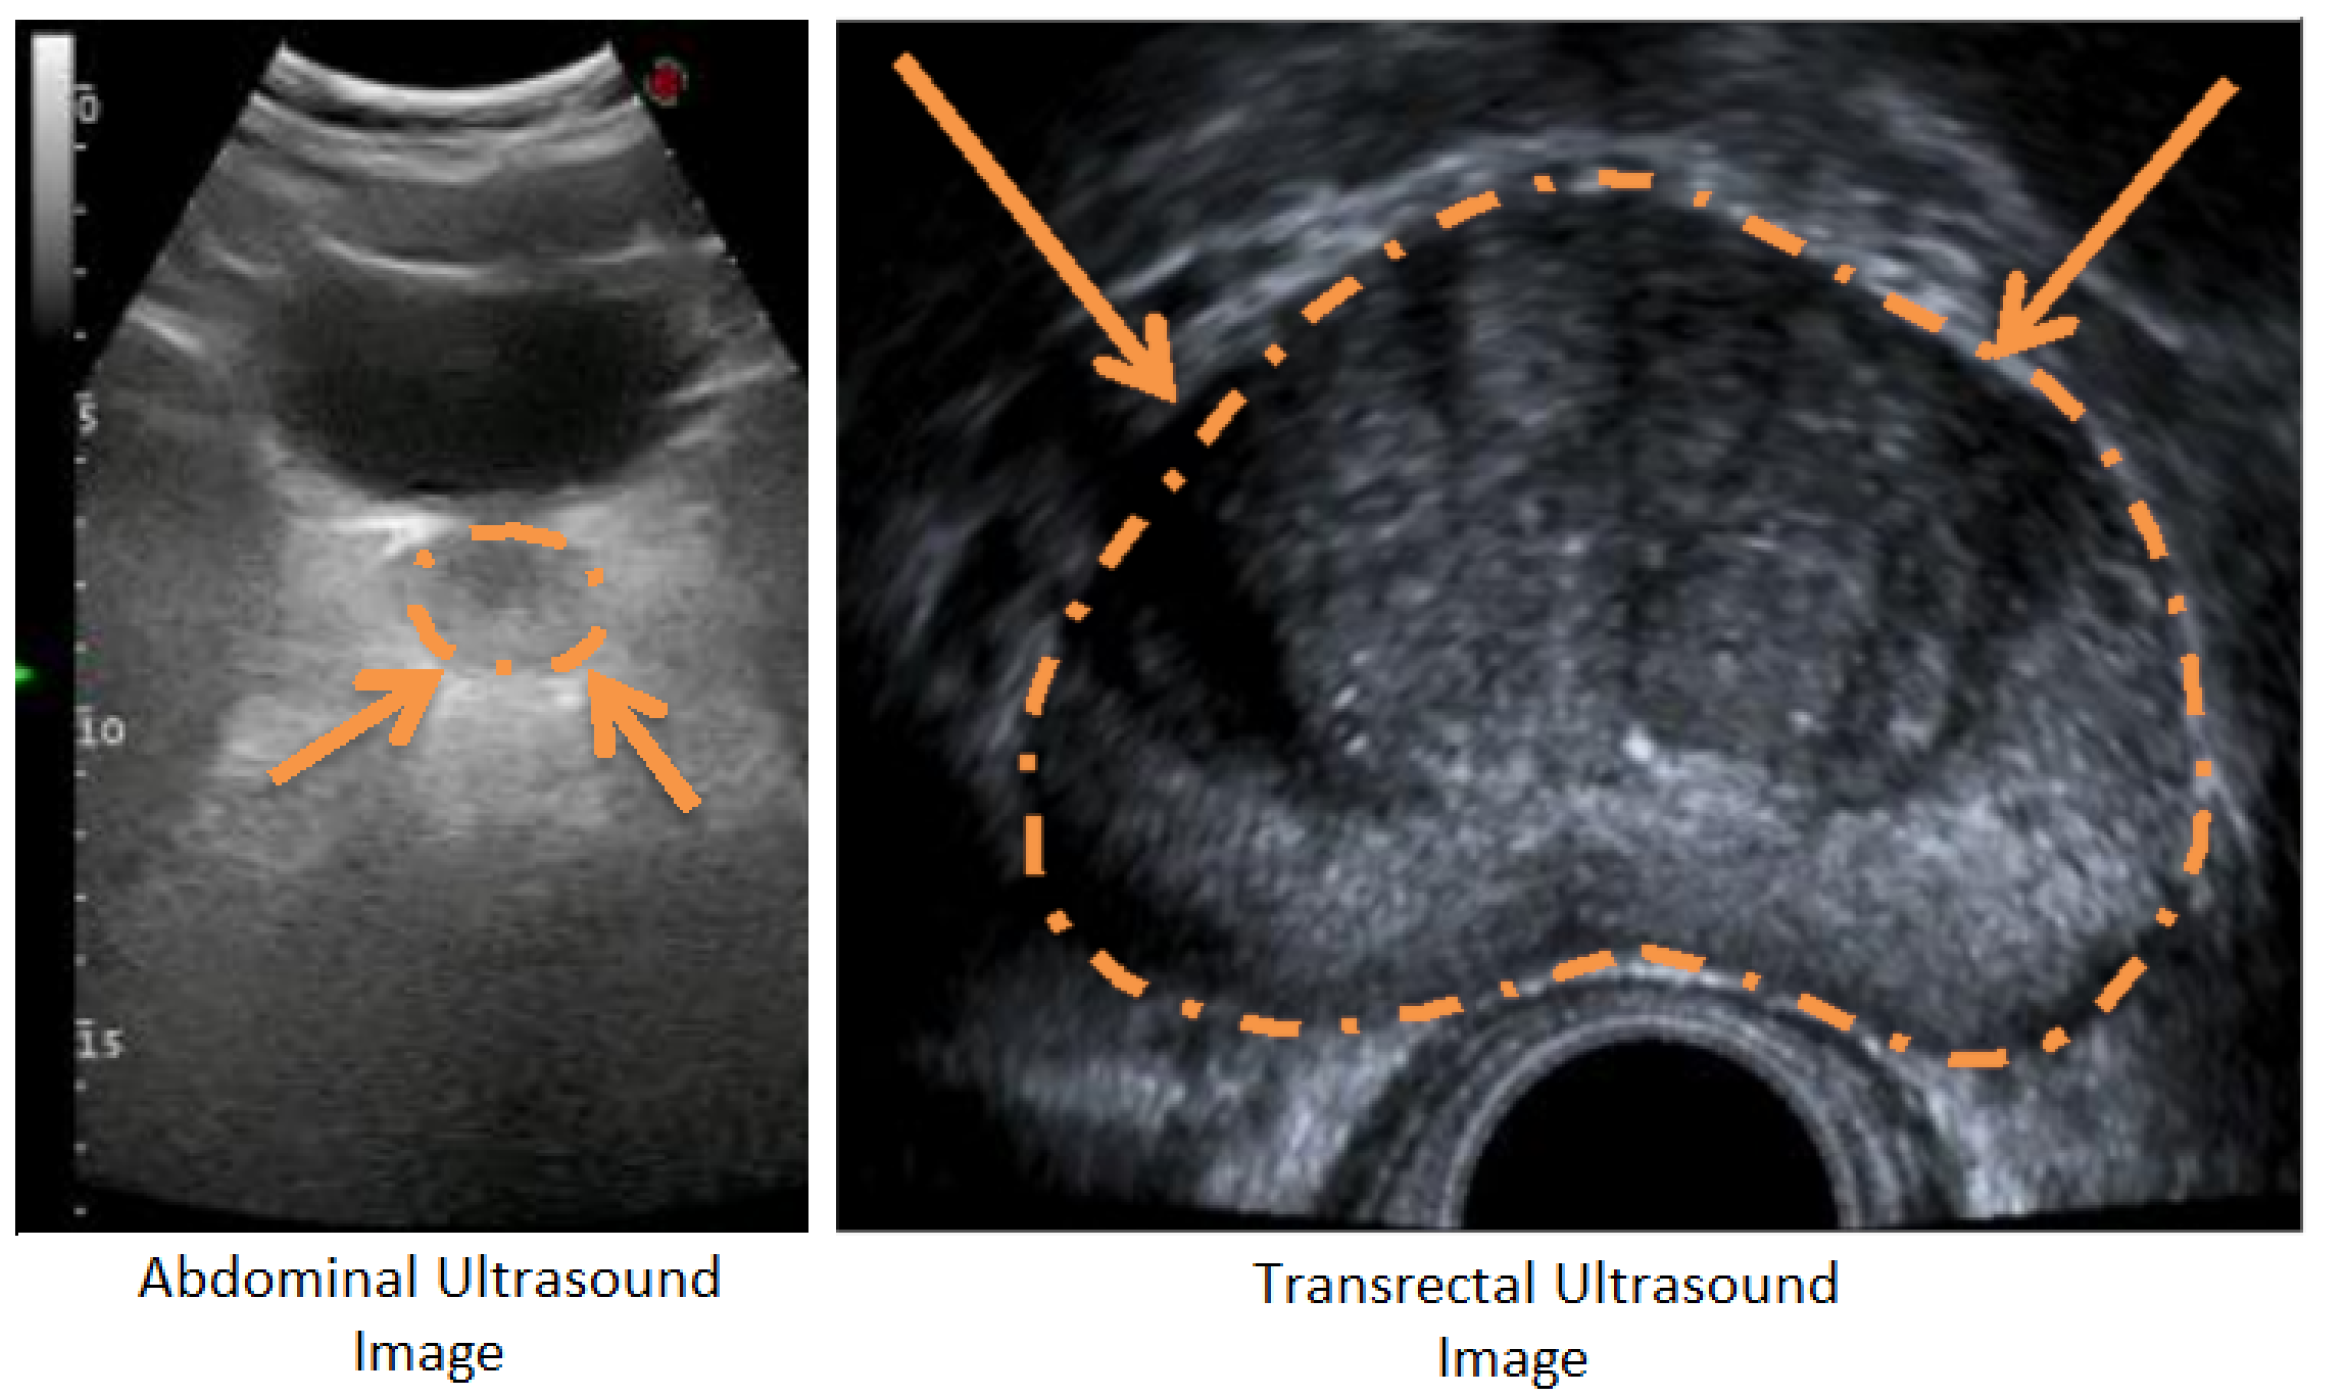

There are many medical-imaging technologies to estimate prostate volume. Widely used technologies are Magnetic Resonance Imaging (MRI), Computed Tomography (CT), and Ultrasound (US) [8]. US technology differs from others with its portability, low-cost, and harmlessness, and it allows experts to scan the prostate in real-time [9]. Trans Rectal Ultrasound (TRUS) and Abdominal Ultrasound (AUS) technologies are frequently used in prostate applications. As shown in Figure 1, despite its better imaging quality with a higher Signal-to-Noise Ratio (SNR) and a larger view of the prostate with no other anatomic structures, TRUS technology is difficult to use regularly during successive radiotherapy sequences [10] due to patient discomfort [11]. The AUS technique is an easy-to-use alternative US imaging technology and is often used where TRUS is not practical.

We were unable to compare our volume-estimation results with other studies as almost no other studies are available to estimate prostate volume from AUS images. Instead, we evaluated the difference in intra- and inter-expert volume estimates on AUS images and compared these values with our system estimates. Due to the higher SNR values and better image quality compared (Figure 2) to both AUS and TRUS images (Figure 1), MR image annotations are considered the gold standard [13] in prostate applications. Accordingly, we also evaluated the intra- and inter-expert volume estimation difference in MR images and compared these values with our system’s volume estimations and expert estimations on AUS images. The results show that our system achieved the volume estimate difference values of human experts.

Figure 1. Comparison of AUS and TRUS images of the prostate from transverse plane. While AUS images have lower SNR and contain other anatomical structures, TRUS images have higher SNR, and the prostate is the only anatomical structure contained.